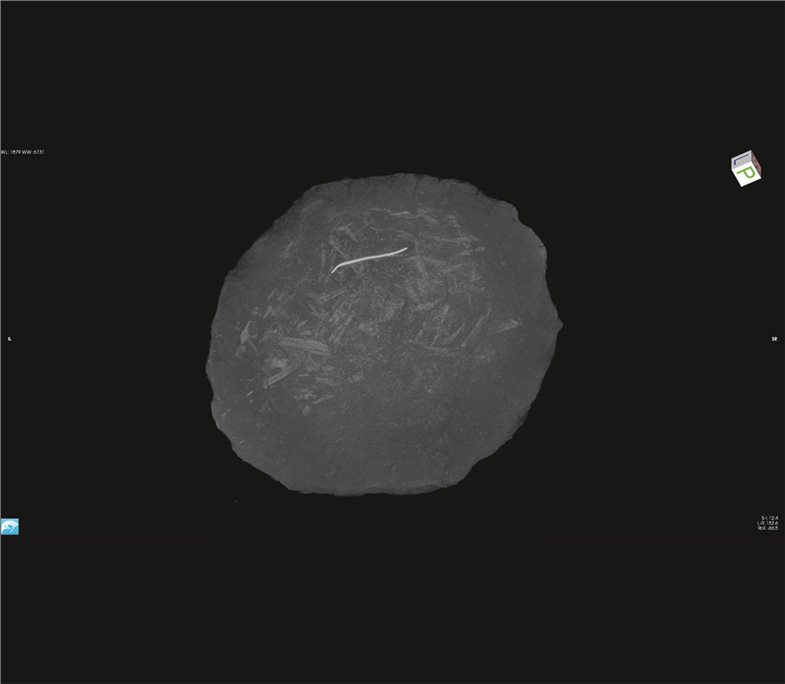

Am Anfang dieser Studien standen konventionelle Röntgenaufnahmen. Da die Gefäße mit Erde gefüllt sind, konnten die Strahlen allerdings nicht durchdringen. Aus diesem Grund wurde das CT-Verfahren herangezogen. Im Gegensatz zur herkömmlichen Verfahrensweise ist dies eine Röntgentechnik, mit der man Schichten im Submillimeterbereich scannen und anschließend Bilder virtuell auf verschiedenen Ebenen oder in dreidimensionaler Darstellung rekonstruieren kann. So konnte auf dem Boden der Urnen das Knochenmaterial erfasst werden.

Obwohl das CT-Verfahren eine gute räumliche Auflösung bietet, können bei diesem Vorgehen Objekte mit ähnlicher Dichte leider nicht gut unterschieden werden. Daher setzten die Forscher erstmals in der Geschichte der Paläopathologie das MRT ein zur Darstellung von menschlichen Überresten aus in der Bronzezeit üblichen Feuerbestattungen, um ein Signal aus dem Leichenbrand aufzeichnen zu können. Mit diesem Schritt ergaben sich gänzlich neue Einblicke in das Innere der Urnen und somit auch in die Anordnung des Leichenbrandes. Während man bislang annahm, dass der Leichenbrand in den Grabgruben angehäuft und anschließend die Urnen kopfüber darüber gestülpt wurden, konnte nun mithilfe der Ergebnisse der gewonnenen CT- und MRT-Scans ein gänzlich anderes Bild gezeichnet werden. Es zeigte sich, dass bestimmte zusammengehörende Bestandteile Leichenbrands innerhalb der Urnen in Gruppen angeordnet waren. Dies lässt darauf schließen, dass die menschlichen Überreste nach der Verbrennung in einem organischen Behälter gesammelt wurden, dieser dann in die Urne gelegt und schließlich zusammen mit derselben umgedreht und bestattet wurde. Auch wenn bislang noch keine Spuren von organischem Material nachgewiesen werden konnten, lassen sich durch eine Reihe von radiologischen Scans eindeutige Ablagerungsmuster erkennen, die auf die beschriebene Art von Behälter hindeuten.

Die Kombination der Methoden zeigt, dass der Leichenbrand in einem organischen Behälter gebündelt am Urnenboden deponiert wurde.

Der harte, trockene Lehmboden des Gräberfelds von Mačkovac verhinderte eine adäquate Ausgrabung an Ort und Stelle. Daher wurden die Urnen intakt und samt Füllung geborgen und für weitere Untersuchungen nach Zagreb gebracht. Um während der anschließenden Mikrograbungen im Labor keine unbeabsichtigten Schäden am Inhalt zu verursachen, wurden konventionelle Röntgenaufnahmen gemacht. Zu sehen war darauf nichts, denn die Strahlen drangen nicht durch die dichte Erde. Schärfere Bilder erhoffte man sich daher vom ­Computertomo­grafen.

Dank der vielen im Submillimeterbereich gescannten Aufnahmen des CTs konnten unter anderem 3D-Rekonstruktionen erstellt werden. Trotz guter räumlicher Auflösung ließen sich Objekte mit ähnlicher Dichte jedoch nicht gut unterscheiden. Ungeahnte Einblicke erbrachten daher die im Anschluss erfolgenden MRT-Scans. Die Kombination der Methoden zeigte, dass der Leichenbrand gezielt und in organischen Behältnissen gebündelt am Urnen­boden deponiert wurde. Auch kleinste ­Metall­objekte konnten geortet und zerstörungsfrei geborgen werden.